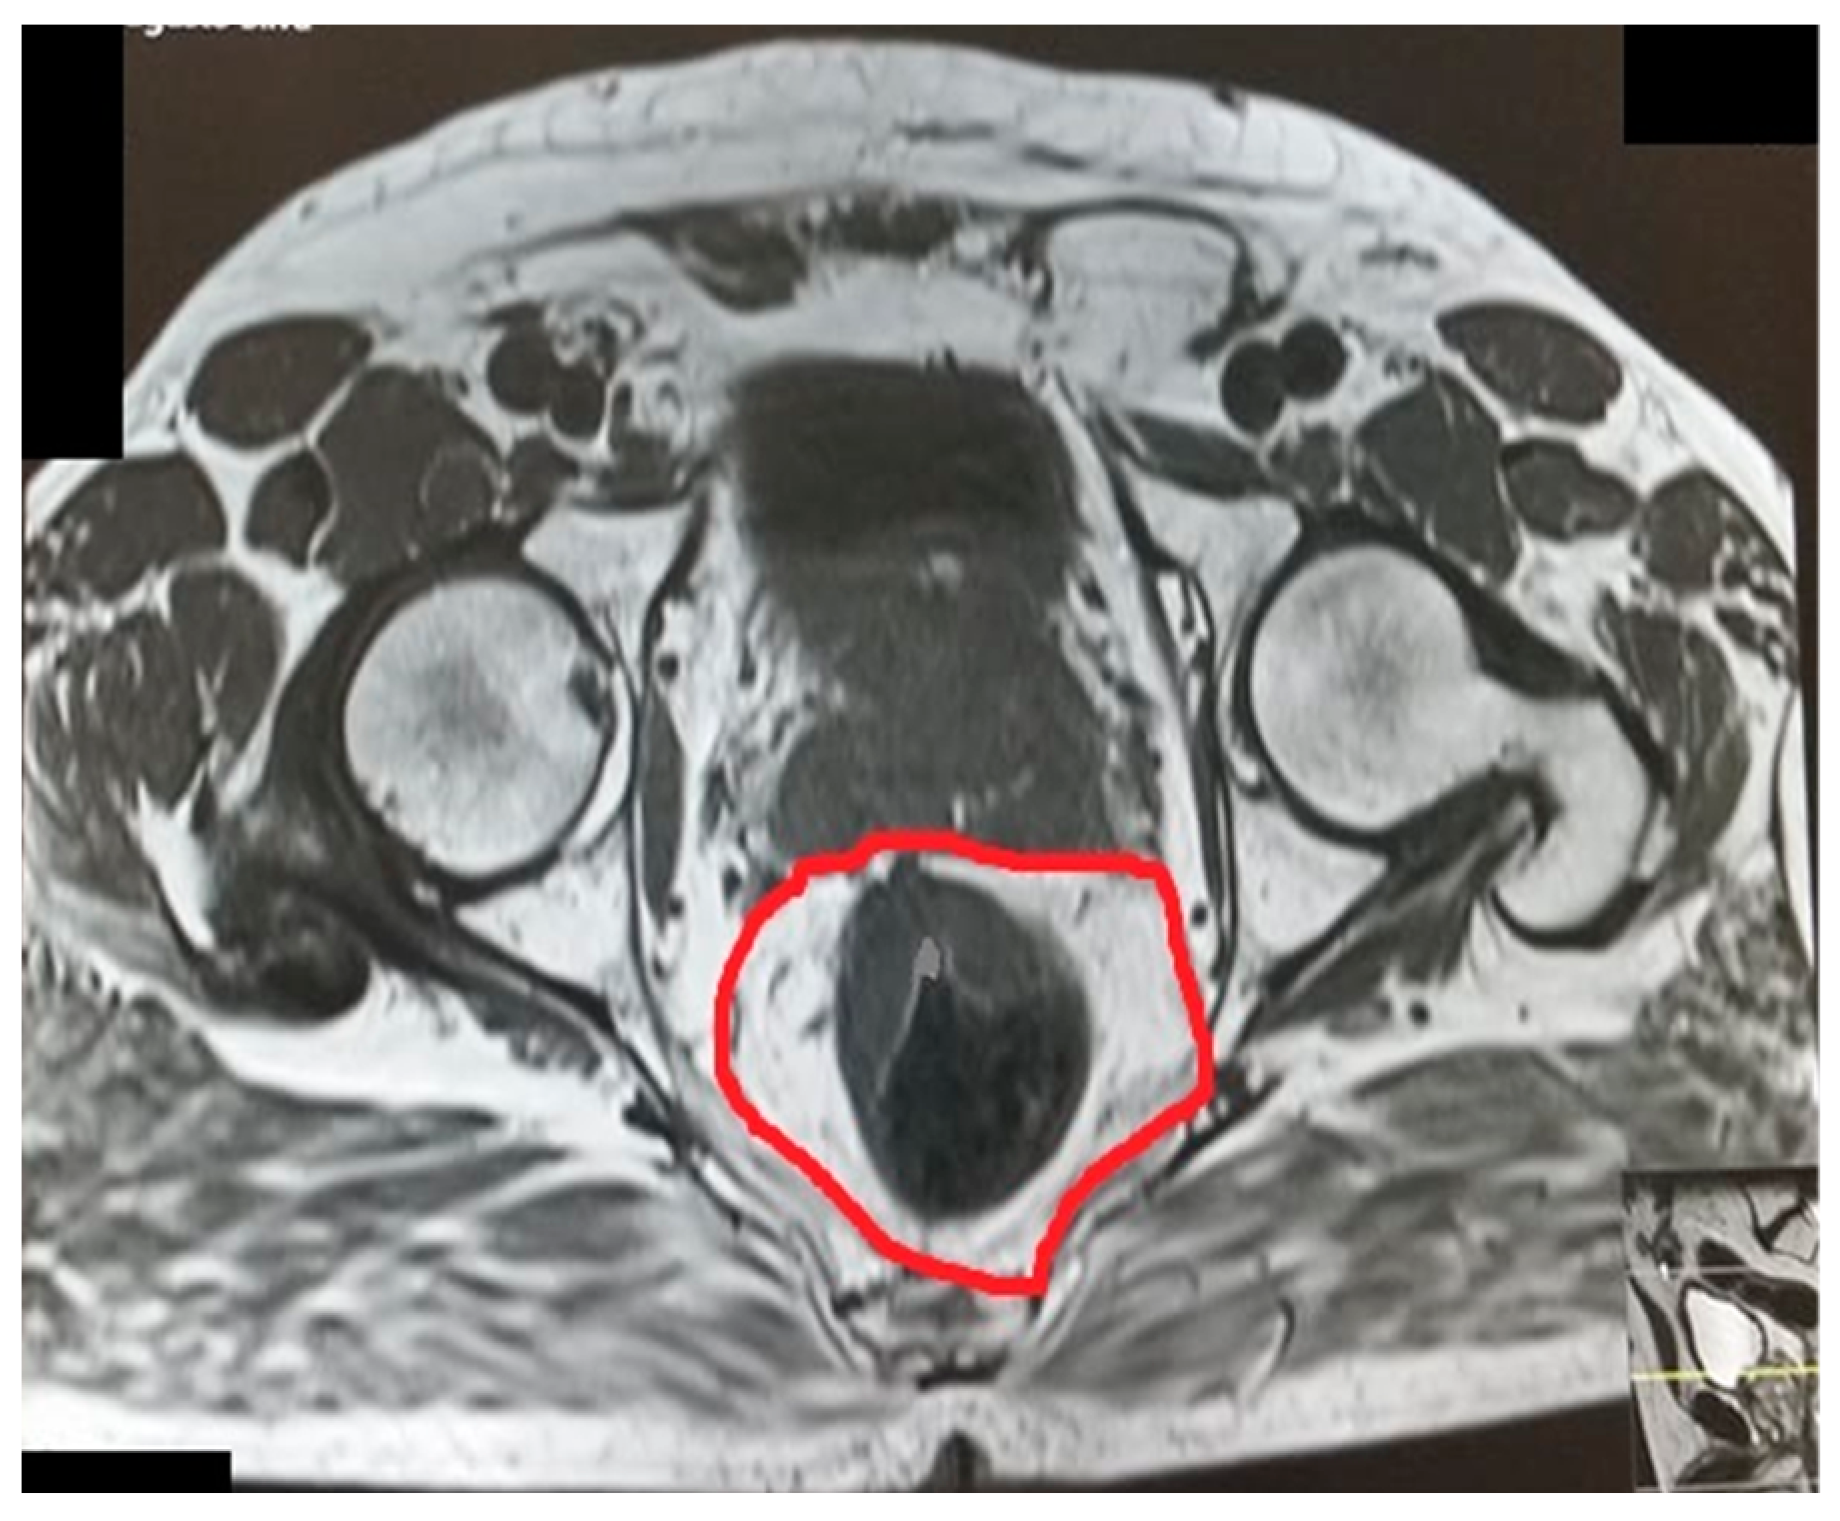

The pelvic measurements on MRI (Figure 2, Figure 3, Figure 4, Figure 5, Figure 6 and Figure 7) were carried out by the author, and to maintain the reproducibility of the results, measurements were taken, whenever possible, at the same anatomical levels.

Figure 5.

Intertuberous distance.